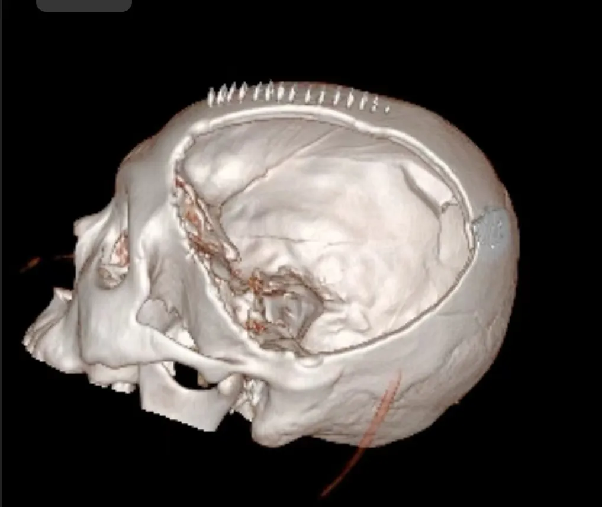

患者术后满三个月再次返院进行颅骨缺损修补术,经过完善术前检查、全科讨论、做好充分手术准备后,武宁县总医院人民医院院区神经外科团队成功为患者完成自体颅骨修补术。

术前: